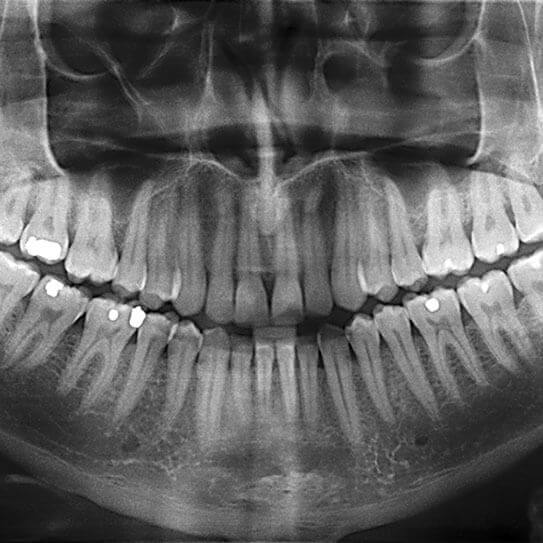

Dental X-Rays: It’s Time For Your Close-Up